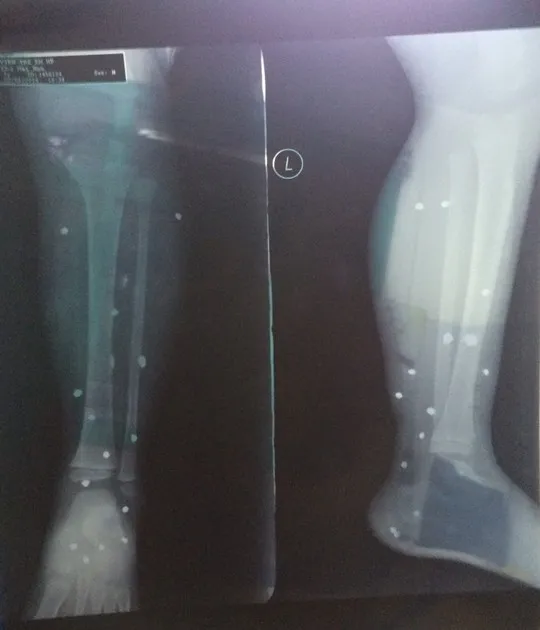

16 mảnh đạn chì đã găm vào chân cháu Nam

Các mảnh đạn chì găm vào chân cháu Nam

Sơ bộ xác định thương tích ở vùng cẳng chân và bàn chân trái của cháu Nam có 16 dị vật (nghi là đạn hoa cải).